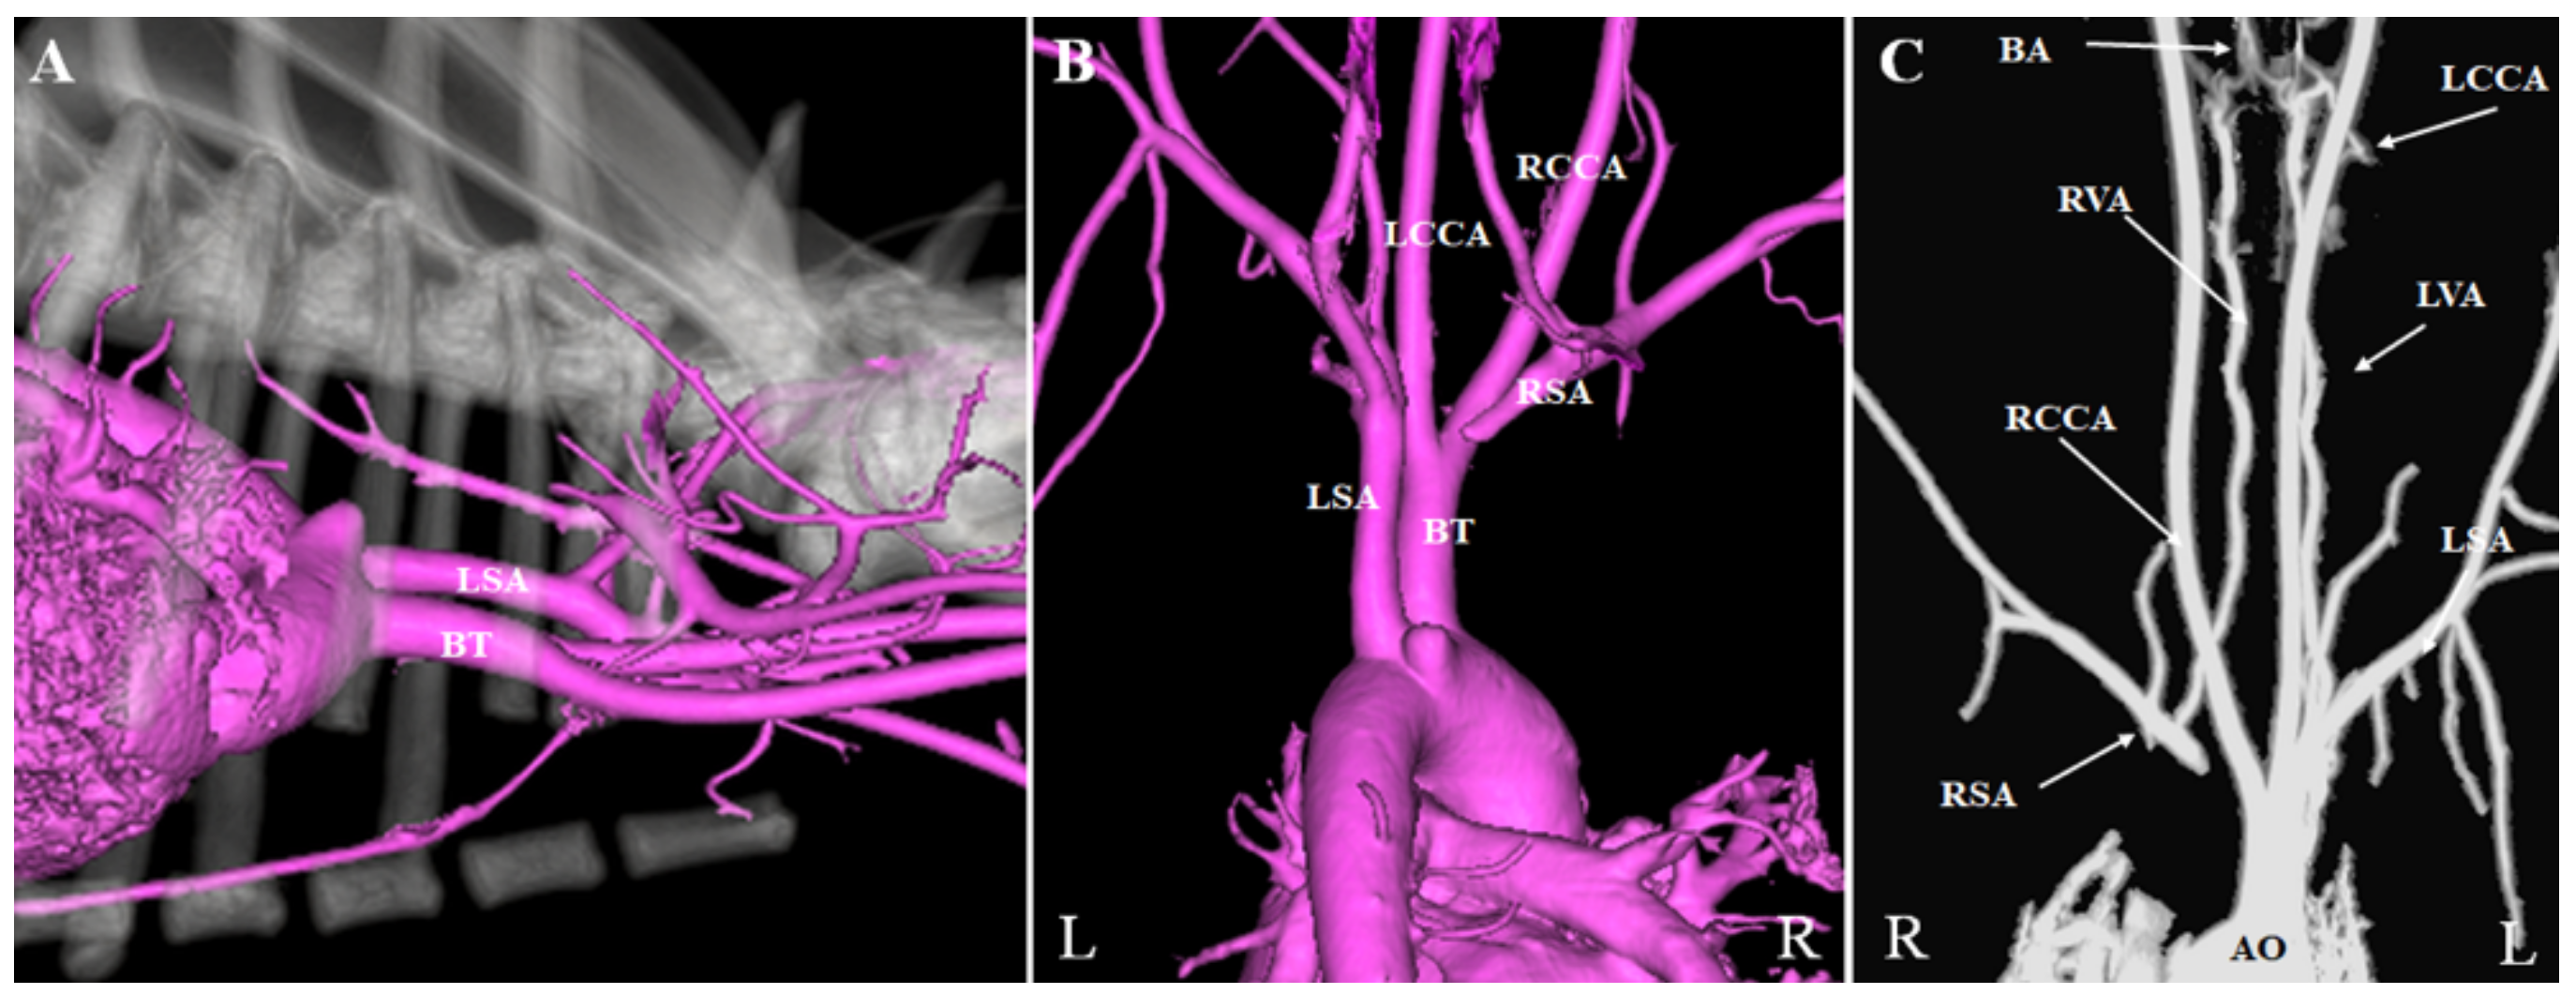

2. Case Presentation